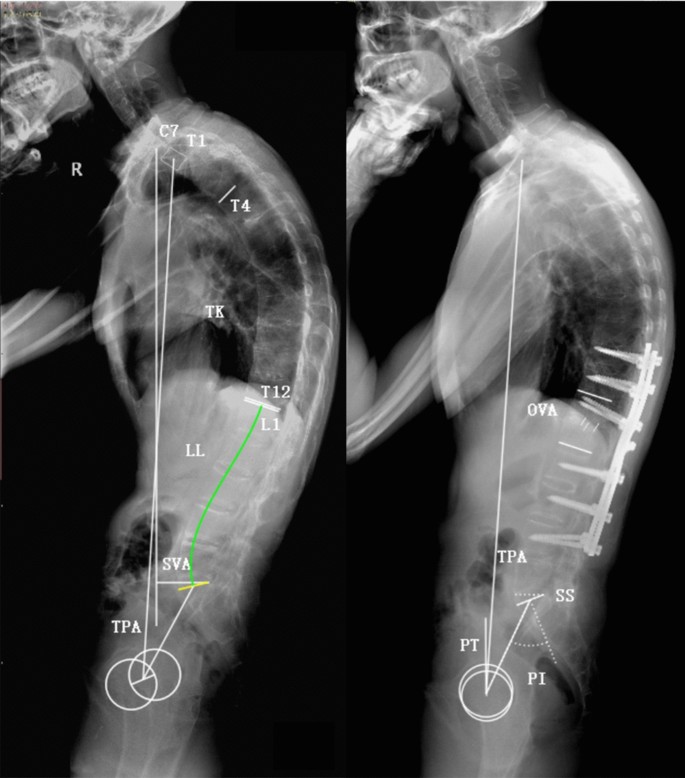

Standing anteroposterior and lateral radiographs of the whole spine were obtained preoperatively and postoperatively (6 months after surgery). The radiographic parameters were measured on lateral radiographs using Surgimap Spine Software (version 2.3.1.3, Nemaris Inc., New York, USA), including thoracic kyphosis (TK), lumbar lordosis (LL), TPA, SVA, osteotomized vertebral angle (OVA) (for two-level osteotomy, OVA was defined as the sum of two Cobb angles measured in two osteotomized vertebrae), pelvic incidence (PI), PT, SS, and PI and LL mismatch (PI-LL) (Fig. 1). All parameters were measured independently by two experienced professionals. PI was considered as a fixed parameter before and after surgery in this study18,19. The demographic and surgical data was collected and recorded for all patients.

Illustration of radiographic parameters measurement. Thoracic kyphosis (TK): the Cobb angle from the T4 upper endplate to the T12 lower endplate; lumbar lordosis (LL): the Cobb angle from the L1 upper endplate to the S1 upper endplate; T1 pelvic angle (TPA): the angle between a line joining the center of T1 and the femoral head axis and a line from the center of the femoral head axis to the midpoint of the S1 upper endplate; sagittal vertical axis (SVA): the distance between the C7 plumb line and the posterosuperior corner of S1; osteotomized vertical angle (OVA): the angle between the lower endplate of the osteotomized vertebra and the upper endplate of the cranial adjacent vertebra; pelvic incidence (PI) : the angle between the line perpendicular to the S1 upper endplate and the line from the center of the S1 upper endplate to the center of the femoral head axis; pelvic tilt (PT): the angle between the vertical line and the line from the center of the S1 upper endplate to the center of the femoral head axis; sacral slope (SS): the angle between the S1 upper endplate and the horizontal line; PI and LL mismatch (PI-LL): the pelvic incidence value minus the lumbar lordosis value.

Predictive ability of the formulae could be applied in surgical plan. The planned PI-LL in regional curvatures achieved by osteotomy, along with the fixed PI, were used to predict the postoperative SS, PT, TPA and SVA. The PI (40.5°) was the only parameter that required to be measured in preoperative radiograph (Fig. 4). With the planned PI-LL (3.0°), the LL was calculated using equation of LL = PI-3.0 = 37.5°. The planned PI-LL and LL were then used to predict SS and PT using the formulae. Subsequently, the TPA and SVA were then predicted with the predictive PT and age (42). The detail of calculation was as follows:

and

A 42-year-old man suffered from thoracolumbar kyphosis secondary to ankylosing spondylitis. (A) Preoperative radiographs showed severe global kyphosis and sagittal imbalance. (B) The patient underwent one-level three-column osteotomy on L2, following which the kyphosis was corrected and the sagittal alignment was restored.

Analysis of the results indicated that the predictive SS, PT and TPA were similar to the postoperative real values (Table 7, Fig. 4). The postoperative real SVA was 8.1 mm larger than the predictive SVA, and it would be closer to the predictive value with lower site of osteotomy.